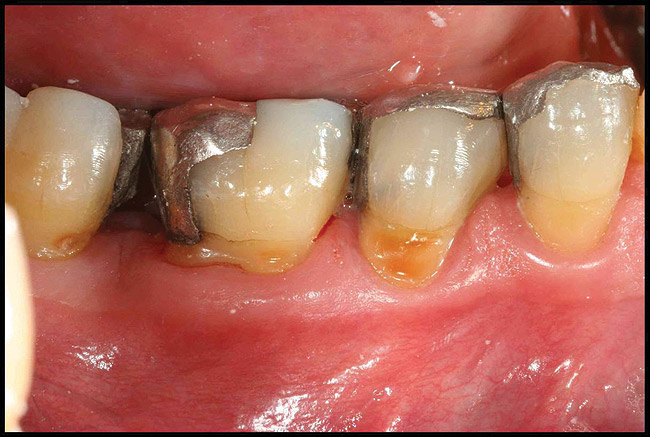

When such findings are encountered during PM, early action should be taken to ensure management. The first step in addressing disease activity is local debridement of the site. For natural teeth, this involves high-quality scaling and root planing, using a combination of ultrasonic instruments and sharp hand curettes to ensure effective removal of plaque and calculus. Human clinical studies have demonstrated ultrasonic instruments have a tremendous advantage over hand instrumentation alone for several reasons. First, accessing the challenging anatomic features of multirooted teeth with furcation involvement is better achieved with ultrasonics.33-35 Second, ultrasonics have been found to be more efficient and equally effective compared to hand instruments when applied to single rooted teeth.33,36 Third, a combination of sonic and hand curette instruments for nonsurgical therapy has been shown to be more effective in calculus removal than either modality used alone.37 Often, a single intervention of nonsurgical therapy is successful in controlling disease activity during the PM phase. Long-term studies have shown that after periodontal surgery, recurrent disease developing during PM responds favorably to nonsurgical therapy in 88% of cases.38

Locally delivered, controlled-release agents are a popular treatment adjunct and serve to augment scaling and root planing to help improve outcomes. Clinical studies have shown that use of such agents can provide an average of 0.5-mm additional pocket depth reduction over scaling and root planing alone, so the practitioner must weigh the cost-benefit ratio of using these products in each patient situation.39,40 A guideline for the appropriate use of locally delivered antimicrobials has been provided by the American Academy of Periodontology.41 These materials are contraindicated in patients with (1) multiple 5-mm pocket depths in one quadrant; (2) anatomic defects caused by periodontal diseases (intrabony defects); and (3) when the previous use of locally delivered agents has failed to control disease. As noted before, a follow-up reevaluation always should be completed to evaluate the success of any therapeutic intervention, generally at 4 to 6 weeks after treatment has been rendered30,31 (Figure 3A through Figure 3D).

Figure 3a   patient in posttreatment periodontal maintenance program returned with (A) isolated bleeding on probing;

Figure 3a

Figure 3b   patient in posttreatment periodontal maintenance program returned with (B) a 5-mm probing depth noted at a maintenance visit.

Figure 3b

Figure 3c  The site was treated by localized scaling and root planing, followed by use of Arestin (minocycline microspheres).

Figure 3c

Figure 3d  The resolution of inflammation and bleeding on probing on the reevaluation appointment 6 weeks later.

Figure 3d